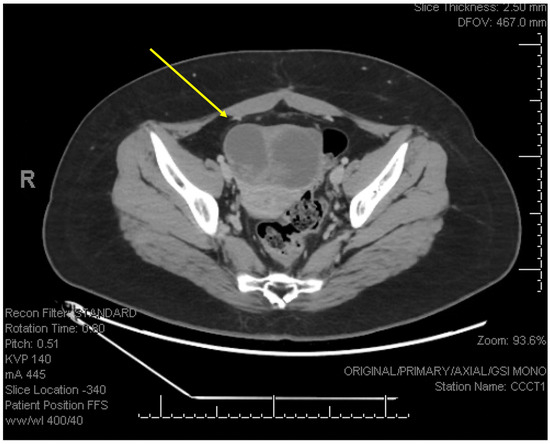

2. Detailed Case Description